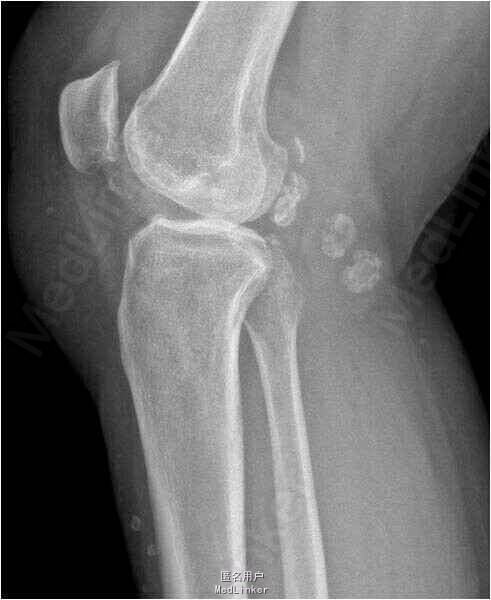

患者男,71岁,因”右膝关节反复疼痛5年余“入院。患者5年前右膝关节无明显诱因出现反复疼痛,偶伴关节绞索,上下楼梯后疼痛加重,休息后稍有缓解,余未见明显异常。

查体:右膝关节活动度20-110°,髌骨加压研磨试验(+)。 X线检查可见右膝关节多发游离体形成。

诊断:右膝关节游离体形成。行关节镜下关节腔清理术及游离体取出术。术后予玻璃酸钠关节腔内注射。